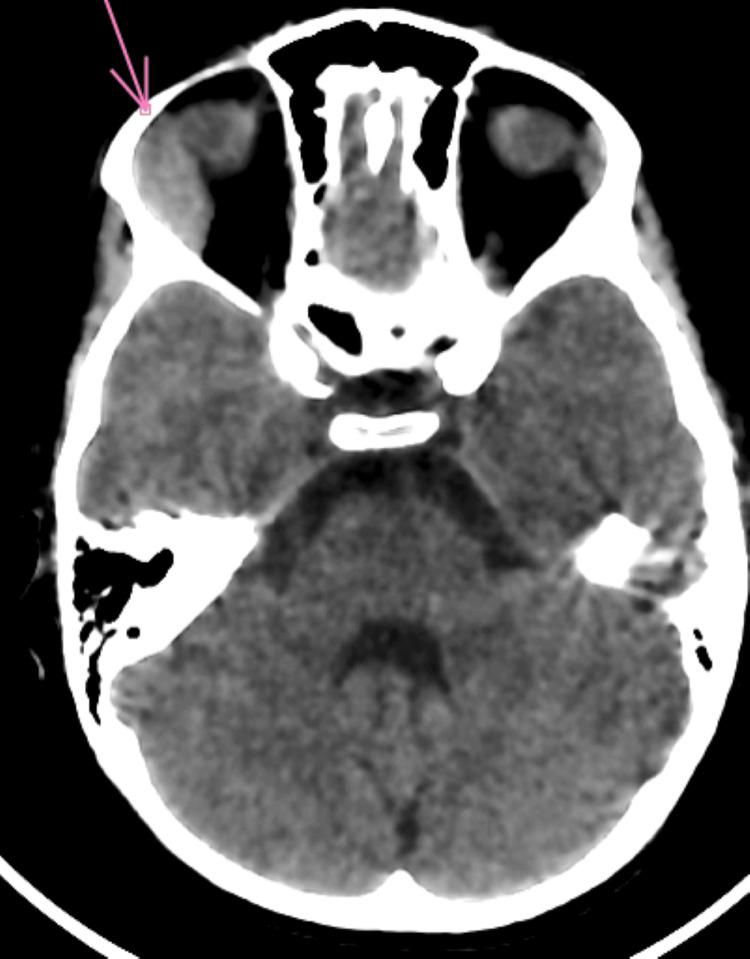

Acute myeloid leukemia (AML) is a malignant hematological condition characterized by the uncontrolled proliferation of immature myeloid cells in the bone marrow, which disrupts the normal production of blood cells. Although it is a relatively rare subtype of pediatric acute leukemia, it is a significant cause of leukemia-related mortality in children. Ocular involvement in acute leukemias, though uncommon, can be a revealing sign of the disease, sometimes presenting as either an initial or secondary manifestation, especially during relapse. We report the case of a five-year-old child presenting with progressive unilateral exophthalmos associated with fever, anemia, and chest pain, signs of general deterioration. Examinations revealed leukocytosis and circulating blasts, suggesting acute leukemia. A bone marrow aspirate confirmed the diagnosis of AML, subtype 2, with multilineage dysplasia. Orbital imaging showed exophthalmos associated with swelling of the lacrimal gland and infiltration of the extraconical fat. Chemotherapy treatment led to complete remission. Ocular manifestations, particularly exophthalmos, are frequently associated with AML and can indicate an aggressive form of the disease or extramedullary localization. Although this presentation generally has a poor prognosis, our case demonstrated a favorable outcome, which is exceptional in the literature. This case underscores the importance of considering leukemia in the differential diagnosis of unexplained exophthalmos in children and the need for rapid diagnostic testing, including bone marrow aspiration, to confirm the disease. Early recognition and appropriate treatment are crucial for improving prognosis.

急性髓系白血病(AML)是一种恶性血液疾病,其特征是骨髓中未成熟髓系细胞不受控制地增殖,这会扰乱血细胞的正常生成。尽管它是儿童急性白血病中相对罕见的亚型,但却是儿童白血病相关死亡的重要原因。急性白血病累及眼部虽然不常见,但可能是该病的一个提示性体征,有时表现为初始或继发表现,尤其是在复发期间。我们报告一例五岁儿童病例,该患儿出现进行性单侧眼球突出,并伴有发热、贫血和胸痛等全身状况恶化的体征。检查发现白细胞增多和循环原始细胞,提示急性白血病。骨髓穿刺确诊为AML,2型,伴有多系发育异常。眼眶成像显示眼球突出伴泪腺肿大和眶锥外脂肪浸润。化疗治疗导致完全缓解。眼部表现,尤其是眼球突出,常与AML相关,可提示疾病的侵袭性形式或髓外定位。虽然这种表现通常预后较差,但我们的病例显示了良好的结果,这在文献中是例外情况。该病例强调了在儿童不明原因眼球突出的鉴别诊断中考虑白血病的重要性,以及进行包括骨髓穿刺在内的快速诊断检测以确诊疾病的必要性。早期识别和适当治疗对改善预后至关重要。